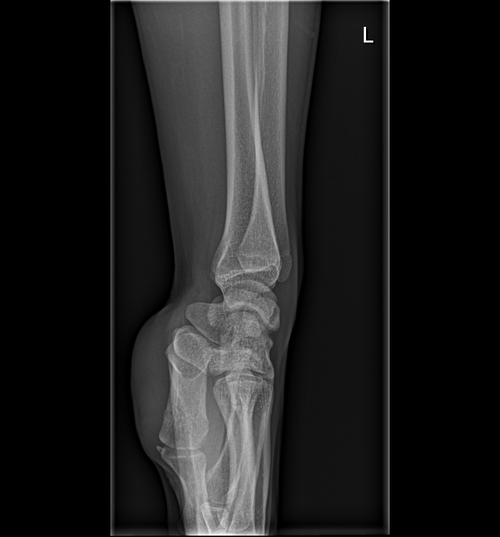

FYI. Im 17yr , 168cm ( 5'6) . my dad is 5'5 and mom is 5'2

the big doc said that my bone age is 17yr old and that my plates are closed but I trust org more then the doctors so here are my results.

is it worth to pin gh or should I accept it?